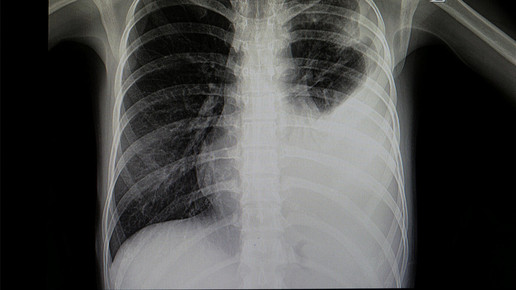

Bei ihrer Arbeit wurde Kopp von ihrem Professor Dr. Alexander Jesser unterstützt. „Bei einer Erkrankung der Lunge ist das betroffene Gewebe meist weniger transparent für die Röntgenstrahlung und kann durch seine Form und Abgrenzung Aufschluss geben, um welche Art der Krankheit es sich handelt. Eine Covid-19-Erkrankung zeigt meist milchglasartige Veränderungen in beiden Lungenflügeln. Ist eine Erkrankung der Lunge durch eine Infektion mit Bakterien erfolgt, ist mehrheitlich nur ein Flügel der Lunge verändert. Eine gleichmäßige Ausbreitung über alle Bereiche der Lunge ist dabei also ein Hinweis auf eine Covid-19 Infektion“, erläutert Jesser.

Damit die Aufnahmen vom Programm ausgewertet werden können, müssen sie in einen Standard-PC eingelesen werden. Danach wird mit einer speziellen mathematischen Operation der Kontrast erhöht. Dadurch können auch qualitativ schlechtere Aufnahmen analysiert werden, die häufig durch ältere Geräte zu Stande kommen. Neben dem Falschfarbenbild erstellt die Software ein sogenanntes „Binärbild“, auf welchem sich bereits die Umrisse der Lunge, sowie Spuren von geschädigtem Gewebe erkennen lassen.

Mithilfe eines weiteren Algorithmus werden die dort vorhandenen Kanten und Grenzen der einzelnen Bereiche ermittelt. Durch weitere Berechnungen werden Flächen- und Symmetriebetrachtungen vollzogen. Dadurch soll letztlich mit großer Wahrscheinlichkeit zwischen bakterieller oder viraler Lungenentzündung unterschieden werden. Dr. Konrad Appelt, Radiologe am Universitätsspital Basel, verweist ebenfalls auf den Nutzen der Software: „Klar ist, dass durch diese Methode ein qualifizierter Arzt nicht ersetzt werden kann und ein einfaches Röntgenbild nicht die diagnostische Qualität eines Computertomographens aufweist, sie kann aber eine sehr sinnvolle, zusätzliche Maßnahme zur Diagnose der Covid-19 Erkrankung sein.“